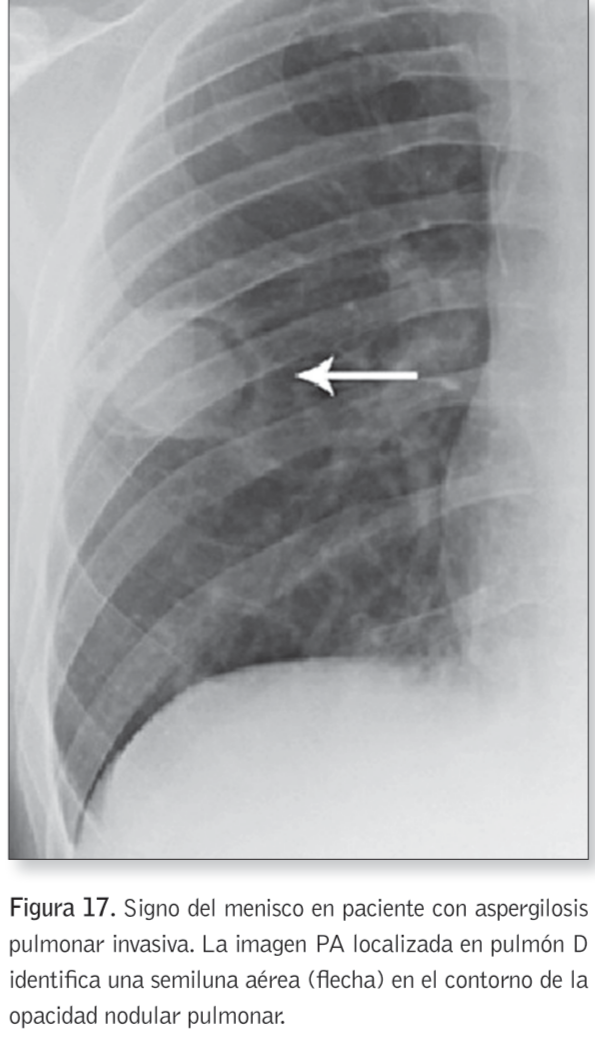

Signo del menisco [aire crescent sign]